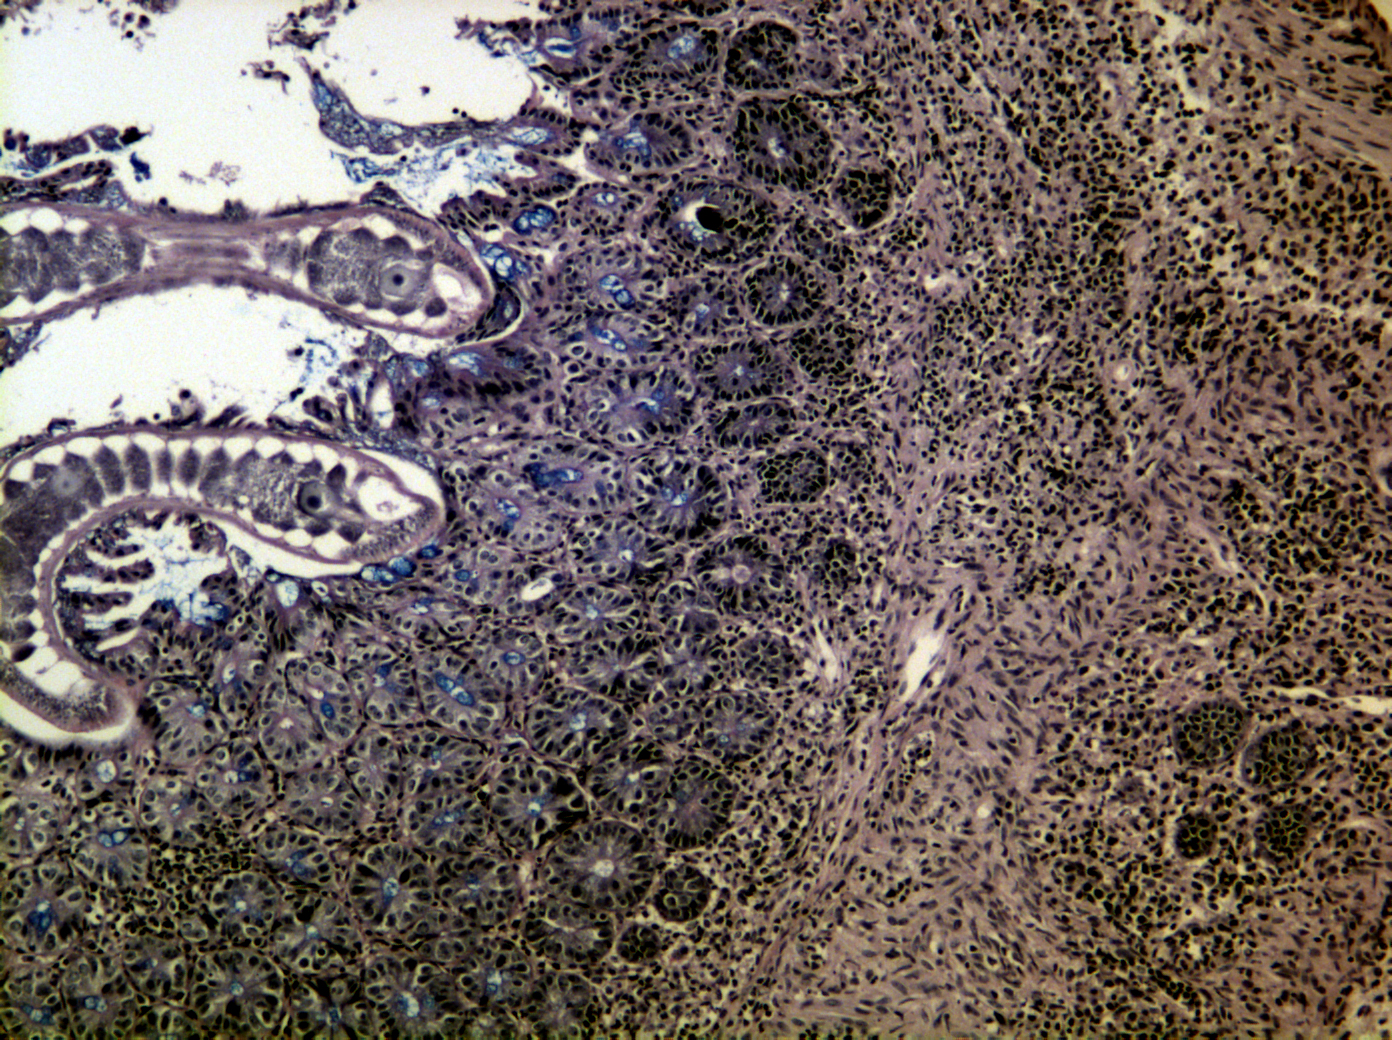

Trichuris muris